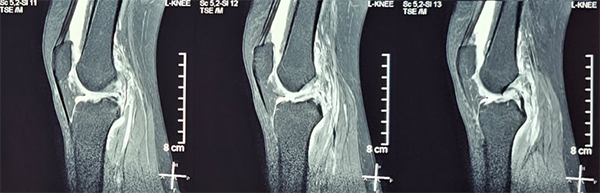

35岁的李女士2个月前不慎扭伤左膝关节,受伤时自感关节脱位感,并闻及韧带撕裂声,随后关节明显肿胀伴活动障碍。约1周后李女士膝关节肿胀、疼痛明显减轻,但快步行走时自觉膝关节不稳,无法跑步、跳跃。李女士到省立医院就诊,体格检查左膝前抽屉试验(+),Lachman试验(+),轴移试验(+),Lever sign test(+),侧方应力试验(-)。左膝关节MR见左膝前交叉韧带撕裂,伴关节积液,股骨、胫骨骨髓水肿。根据患者体格检查及影像检查结果,患者诊断为“左膝前交叉韧带撕裂”,需行手术治疗。